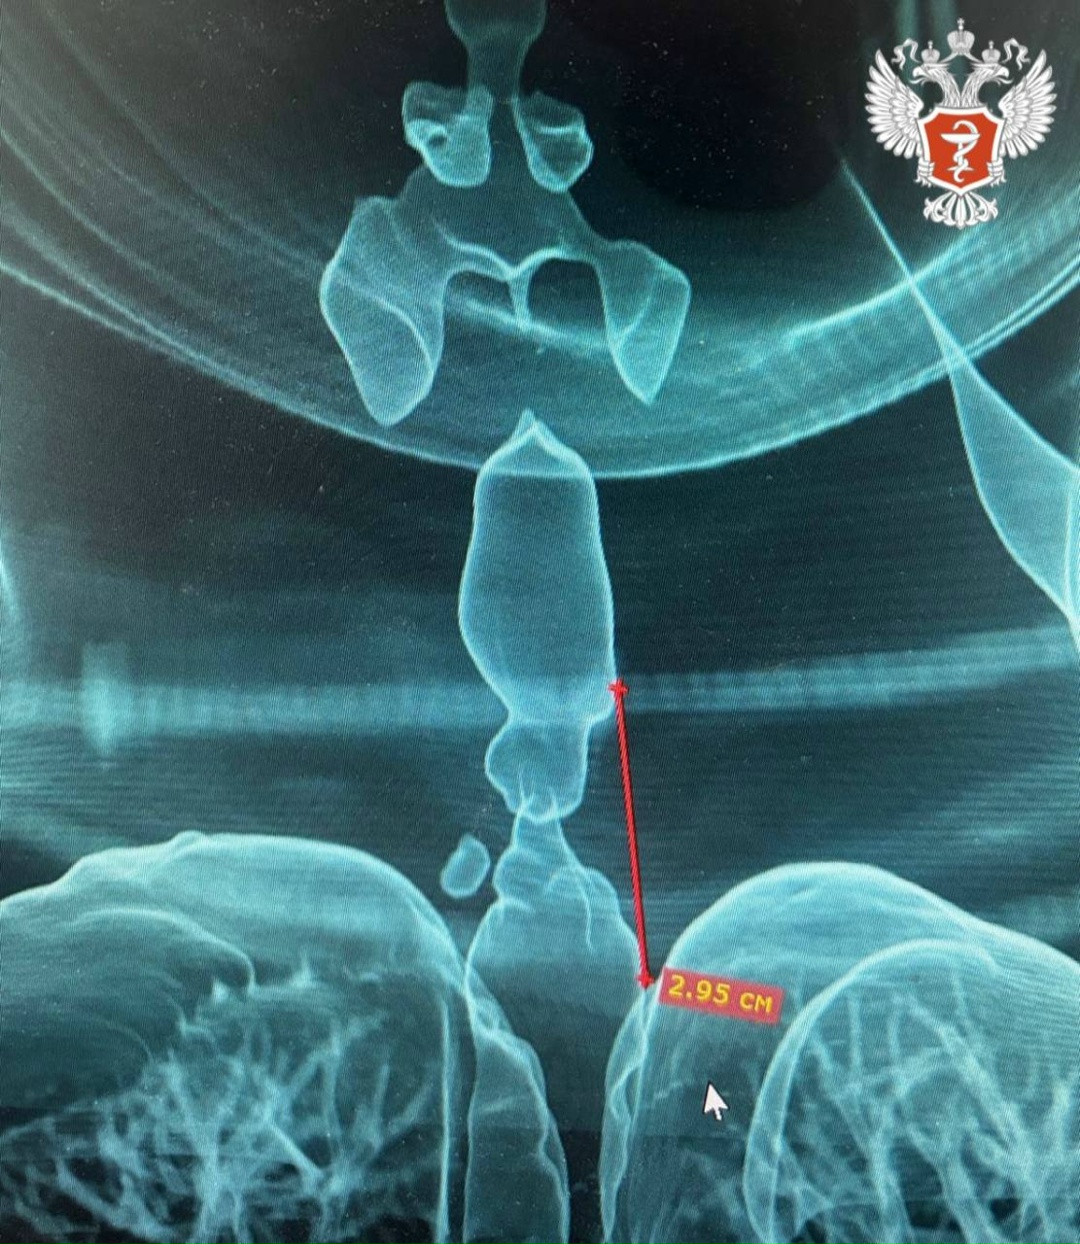

Чтобы получить более точную оценку протяжённости и расположения сужения, специалисты Городской клинической больницы №9 создали 3D-модель дыхательных путей пациентки.

📌 Протяженность стеноза составила 2,95 см, а минимальный просвет трахеи — всего 5 мм. Такая ситуация угрожала жизни пациентки и требовала проведения срочной операции.